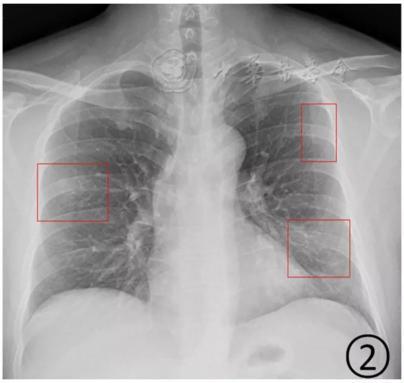

其實,在疾病早期,肺部CT上可能并不會首先出現磨玻璃影。華中科技大學同濟醫學院附屬同濟醫院放射科管漢雄教授發文稱,患者一旦出現咳嗽、持續發熱、不明原因乏力時,CT常常會有陽性發現。肺部CT上可能出現一白色不規則的小斑片(如圖1箭頭所指區域),即“實變結節影”,或者是中央實變、周圍磨玻璃(如圖2箭頭所指區域),也就是中央區域是一白色不規則的小斑片,周圍則像云霧狀磨砂玻璃一樣。隨著病毒的持續“攻擊”,病情發展,感染加重,白色的實變結節區域開始吸收,如同一顆糖融化了一樣,慢慢變為磨玻璃影。

▲圖1:肺部CT上出現一白色的小斑片;圖2:中央區域是一白色的小斑片,周圍則像云霧狀磨砂玻璃一樣(圖片來自網絡)

根據感染程度不同,有的僅單側肺出現這種磨玻璃影,還有的雙側都有。磨玻璃影可以累及一個肺葉,也可同時累及多個肺葉。

▲上面的圖:單側肺出現磨玻璃影,累及一個肺葉;下面的圖:雙側肺均出現磨玻璃影,累及多個肺葉(圖片來自網絡)

上海市胸科醫院放射科主任醫師于紅在接受媒體采訪時介紹,新冠肺炎的影像特征與其他病毒性肺炎相似。早期患者肺部多會出現單個或多個小斑片影、局灶性磨玻璃影等。隨著病情進展,病灶增多并融合,范圍擴大,多個肺葉出現小斑片,或者表現為彌漫性磨玻璃影及實變結節影。

按照國家衛健委發布的新型冠狀病毒肺炎試行第六版診療方案之中的臨床分型,新冠肺炎分為輕型、普通型、重型及危重型。在患者的肺部CT中,輕型者沒有比較明顯的肺炎改變;普通型者以肺部出現局限性斑片狀或很多節段性片狀“病灶”為主(圖②);重型者雙肺可出現較多的白色小斑片“病灶”,部分融合成大片狀“病灶”(圖③);危重型者會有“白肺”表現(圖④)。

▲從上到下依次為普通型、重型及危重型新冠肺炎患者的肺部CT表現(圖片來自網絡)